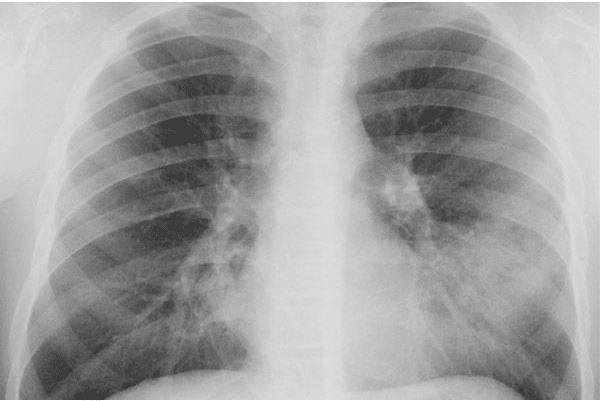

Рентген-признаки микоплазменной пневмонии / © Монастырщинская центральная районная больница